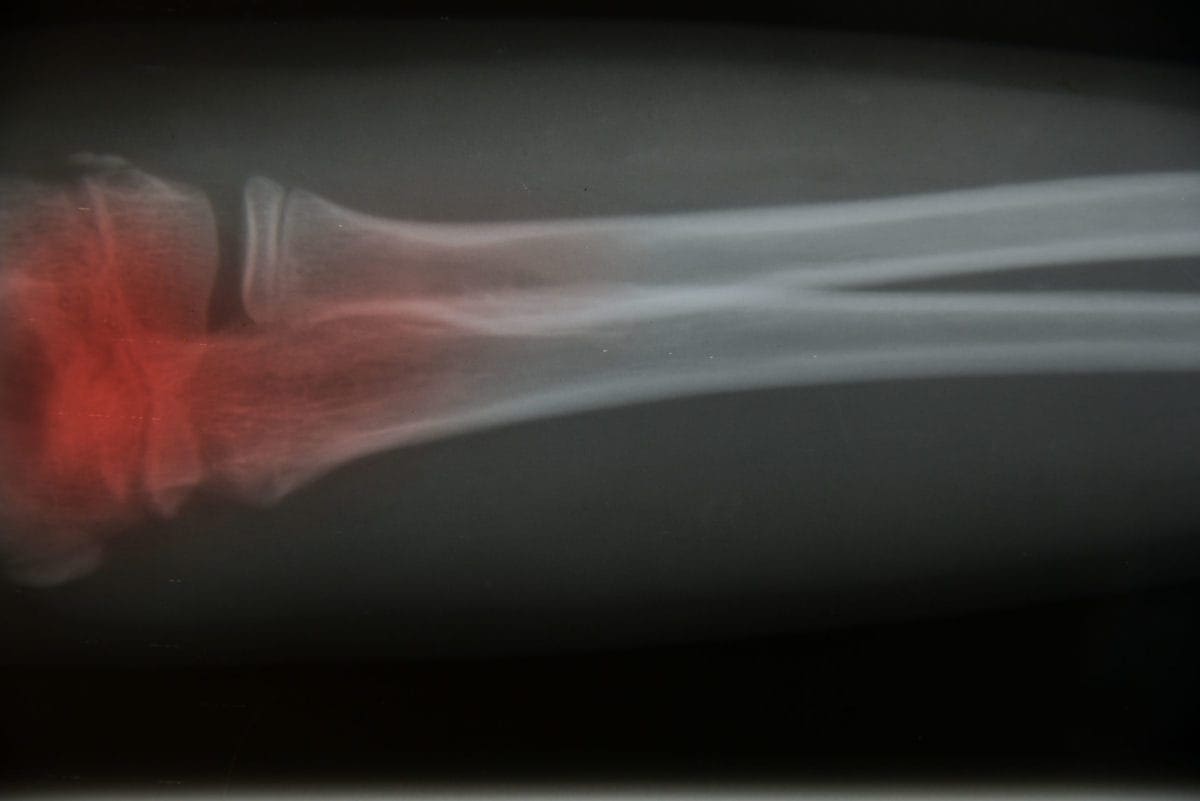

Bone Cancer | Symptoms and Treatment

Bone cancer is a rare but serious condition that starts in the cells of your bones. Knowing the common bone cancer symptoms and treatment options can help you recognize warning signs early and get the right care. With early diagnosis and a personalized treatment plan, many people can manage the condition and improve their quality of life.

Symptoms of bone cancer

The main symptom of bone cancer is pain. However, not everyone has pain. You also may have swelling in the area where bone cancer exists, fractures, or high levels of calcium in the blood. Other symptoms include:

How is bone cancer diagnosed?

There are several tests your doctor may do to look for and diagnose bone cancer. If the doctor finds a tumor, they will need to find out if it is cancerous or not. These tests may include:

• X-rays